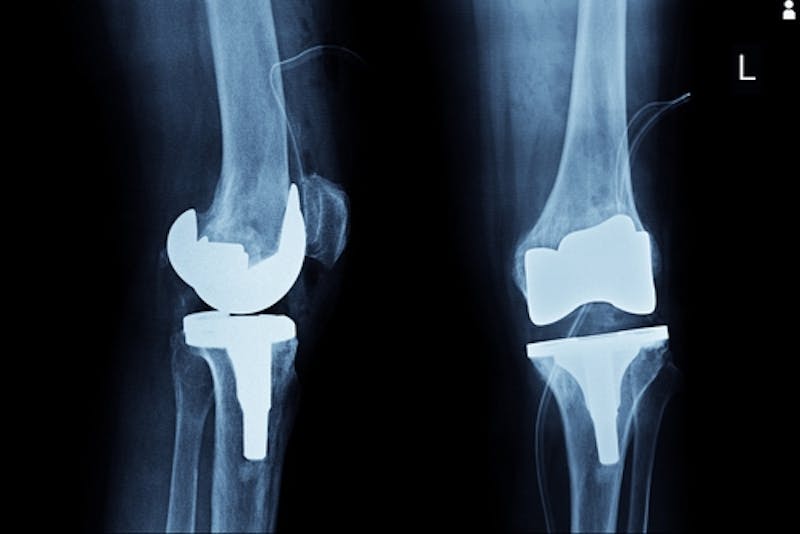

What is the Exactech Knee Device that has been Recalled?

Knee replacements are some of the most common surgical procedures that take place in the United States. In fact, knee replacement surgery is often recommended for patients who suffer from conditions like arthritis, osteoarthritis, hemophilia, and avascular necrosis. There are hun...

Exactech Issues Massive Recall of Knee, Hip, and Ankle Devices

Some of the most routine surgeries performed in many hospitals are knee, hip, and ankle replacements. There are over 600,000 knee replacement surgeries carried out by surgeons every year in the United States. Medical industry statistics reveal that over 2. 5 million patients live ...